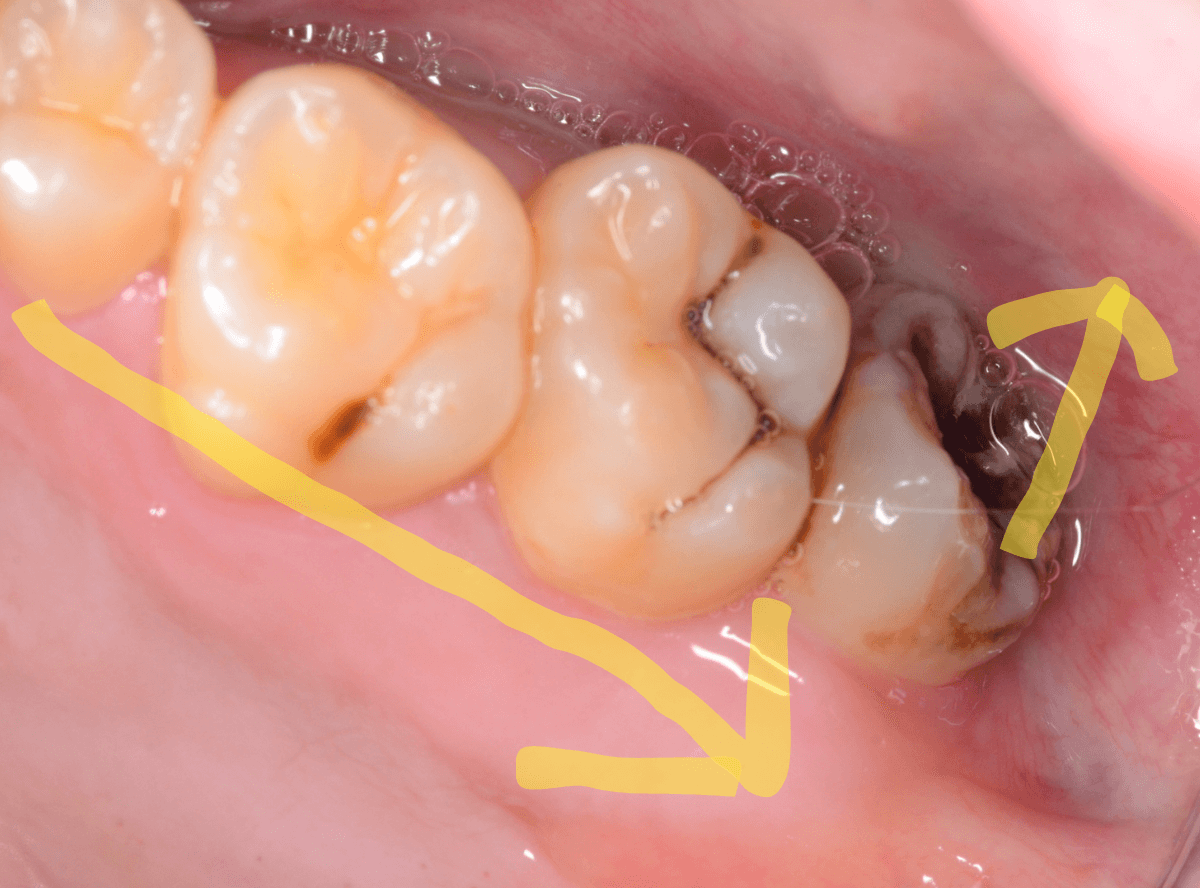

抜歯後に長期間お痛みが出たり、経過観察が必要な難しいおやしらずの抜歯ならまだしも、簡単なおやしらずの抜歯を避けてしまったがために、他の歯に悪影響を与えてしまったもったいない例も多々見てきました。

ここでは、比較的簡単なおやしらずの抜歯の例を中心にご紹介します。

このようなおやしらず、あなたはありませんか?